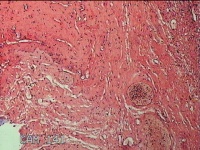

右侧外阴囊肿囊壁

性别

女

年龄

35岁

临床诊断

右侧前庭大腺囊肿

一般病史

发现右侧外阴囊肿1年。

标本名称

大体所见

白暗红色囊性肿物2.3x1.5x0.8cm一个,表面光滑,部分已切开,囊内容物已流失,囊壁厚0.1cm。